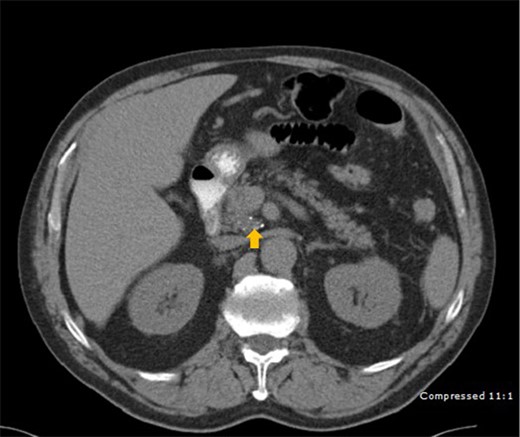

A 78-year-old male who was previously treated for large MCL was referred to our institute after his restaging PET-CT scan showed an increased uptake in a peripancreatic node. His past medical history included prostate cancer treated with prostatectomy. He complained of fatigue, night sweats, weight loss, and abdominal pain. A CT scan revealed a centrally located mass in the head of the pancreas (Fig. 1). Endoscopic Ultrasound (EUS) revealed a 2.1 cm mass at the junction of the pancreatic body and head and peripancreatic lymph node 9.4 mm. FNA of the pancreatic mass showed scattered pleomorphic malignant cells with hyper-chromatic nuclei, prominent nucleoli and scant to moderate amount of cytoplasm. Multinucleated giant cell forms were also present (Fig. 2).

CT scan depicting a 2.5 cm mass (arrow) with calcification in the head of pancreas.